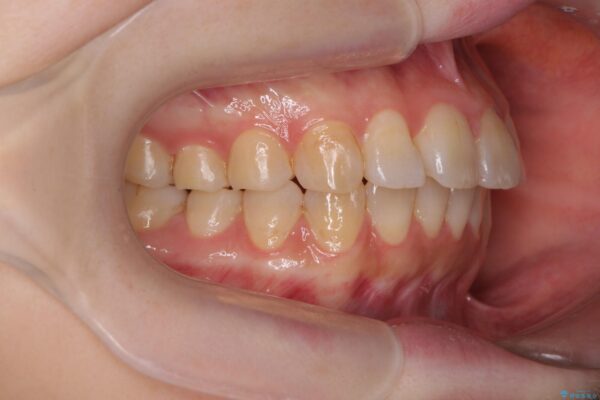

治療前

傾いた前歯、インビザラインで改善 治療前画像 傾いた前歯、インビザラインで改善 治療前画像 傾いた前歯、インビザラインで改善 治療前画像 傾いた前歯、インビザラインで改善 治療前画像